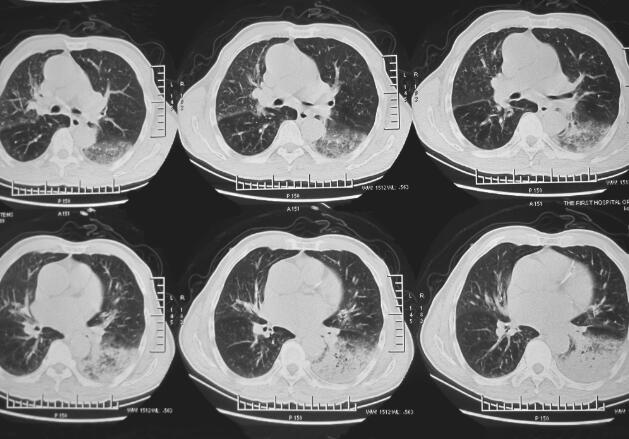

入院后给予抗感染(左氧氟沙星+头孢哌酮舒巴坦+伏立康唑)、祛痰等治疗,咳嗽、咳痰,间断发热等症状改善不明显。2014年3月7日肺部CT(图5)提示慢性支气管疾病肺气肿,伴双肺感染,左下肺不张。2014年3月11日支气管镜检查提示支气管腔内未见明显异常,左下叶黏性分泌物较多。保护性毛刷刷检培养无致病菌生长。2014年3月19日CT引导下经皮肺活检送病原学检查及病理检查提示黏液腺癌,组织培养无致病菌生长。

图5 2014年3月7日肺部CT提示左下肺大片状及右上叶片状阴影